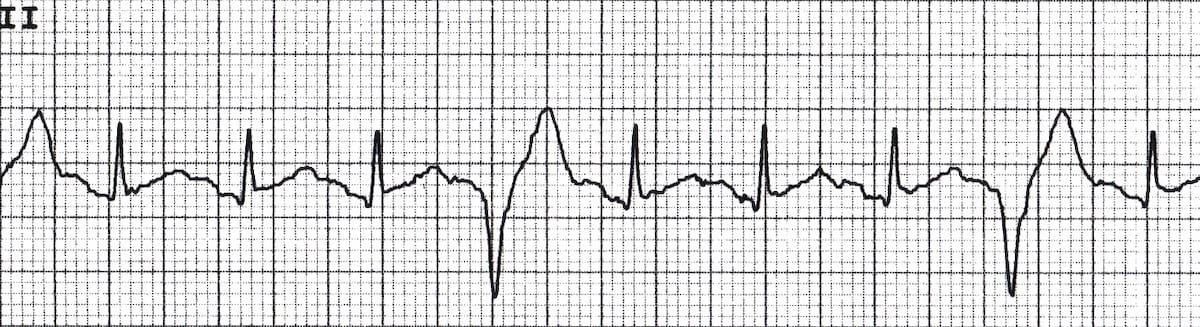

Multifocal PVCs

- Sinus rhythm with PVCs of two different morphologies (arrows)

- Note the appropriately discordant ST segments / T waves

- The pause surrounding the PVC is equal to double the preceding R-R interval (= a full compensatory pause)